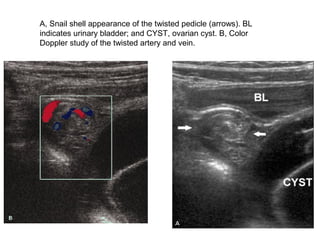

A, Snail shell appearance of the twisted pedicle (arrows). BL

indicates urinary bladder; and CYST, ovarian cyst. B, Color

Doppler study of the twisted artery and vein.